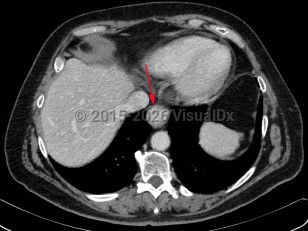

Esophageal carcinoma is a malignancy arising from the esophageal mucosa. There are 2 major histologic types: squamous cell carcinoma (SCC) and adenocarcinoma.

- SCC – Has a striking geographic distribution spanning from China to parts of Iran, central Asia, Afghanistan, Siberia, and Mongolia. Exists in the United States, where it is more common in individuals of African descent than those of Northern European descent and in males than females, and tends to affect people of lower socioeconomic status. Tends to arise in the cervical and thoracic portion of the esophagus. Risk factors include alcohol intake and cigarette smoking, with these factors acting synergistically to increase risk. The risk factors account for around 90% of SCC in the United States.

- Adenocarcinoma – There has been an increase in incidence, with this histologic phenotype accounting for 75% of all new esophageal carcinomas. More common in males of Northern European descent with a male-to-female ratio of 6:1. Arises within the dysplastic columnar epithelium of the distal esophagus, particularly at the gastroesophageal junction, with gastroesophageal reflux disease and Barrett esophagus being primary risk factors.